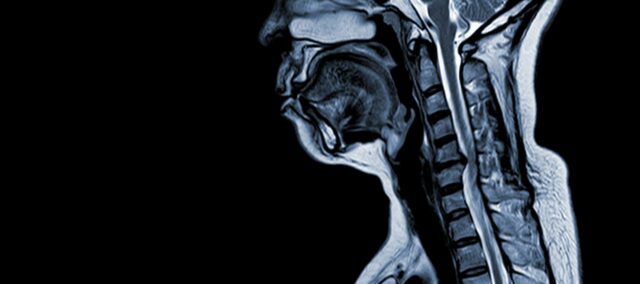

A mielopatia espondilótica cervical (MSE) é uma condição neurológica que é a principal causa de lesão da medula espinhal em adultos. Em termos simples, ela envolve a compressão ou o dano da medula espinhal no pescoço, principalmente devido ao processo natural de envelhecimento que afeta as vértebras cervicais. O termo "mielopatia" deriva das palavras gregas "myelon", que significa "medula espinhal" e "pathos", que significa "doença".

- Degeneração do disco (disco protuberante): A CSM geralmente começa com a degeneração dos discos intervertebrais na coluna cervical, fazendo com que eles se projetem para dentro do canal espinhal.

- Formação óssea subperiosteal (Ventral ao canal espinhal): Em resposta ao aumento do estresse mecânico, o corpo forma um novo tecido ósseo no lado frontal (ventral) do canal espinhal, possivelmente estreitando o espaço para a medula espinhal.

- Ossificação do ligamento longitudinal posterior: O ligamento longitudinal posterior pode sofrer ossificação, endurecimento e calcificação, contribuindo para o estreitamento do canal espinhal.

- Hipertrofia do ligamento amarelo: A hipertrofia do Ligamentum Flavum faz com que ele engrosse e se torne menos flexível, invadindo ainda mais o espaço dentro do canal espinhal e comprimindo a medula espinhal.

Essas alterações estruturais coletivamente levam à compressão e ao estreitamento do canal espinhal, resultando nos sintomas característicos e nas complicações associadas à CSM. O reconhecimento desses fatores de risco e a compreensão dos mecanismos fisiopatológicos envolvidos são essenciais para a prevenção e o gerenciamento. O diagnóstico precoce e as intervenções adequadas são fundamentais para atenuar os efeitos dessas alterações estruturais na medula espinhal.